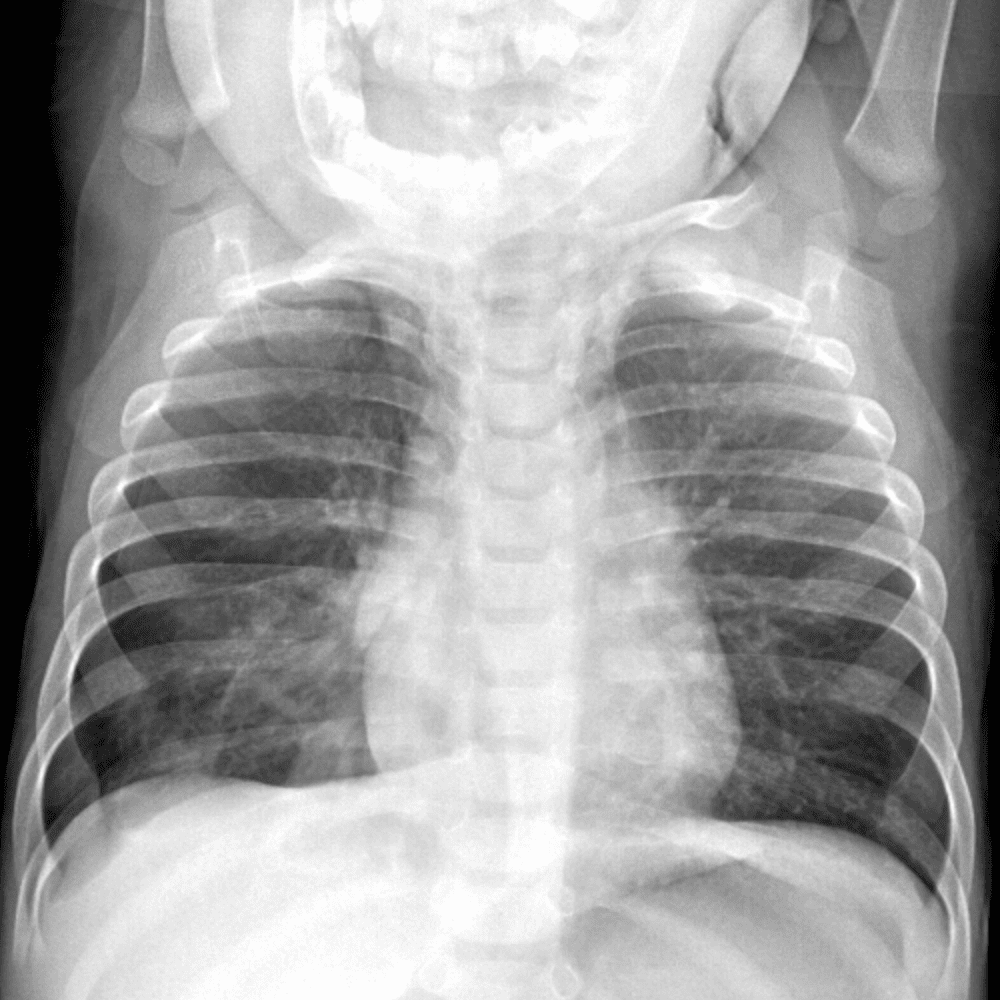

Peds Chest

Practice

Simulates call by including subtle or difficult cases and some normals.

50 cases